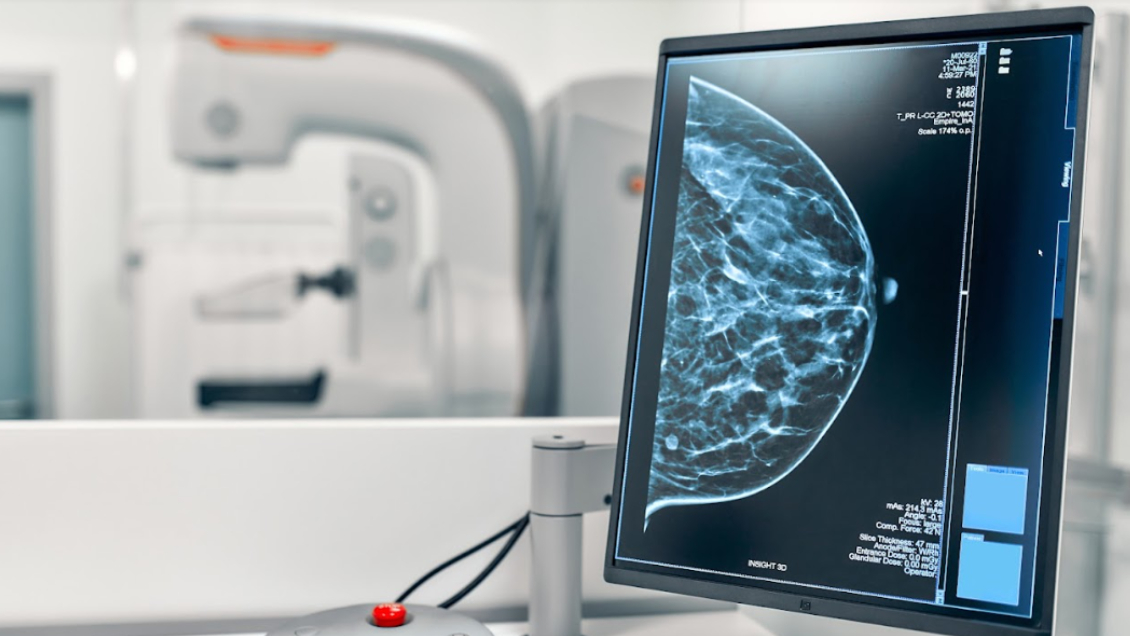

"La mamografía en sí es una sola, pero existen diferentes técnicas de este examen. Algunas son más nuevas, como la mamografía digital, la mamografía con tomosíntesis (avanzados rayos X) y la mamografía con contraste. Tanto la digital como la con tomosíntesis se usan en pacientes asintomáticos como tamizaje (pruebas de detección). En cambio la con contraste tiene indicaciones particulares para pacientes de alto riesgo con sospecha de patología mamaria maligna, y debe ser solicitada por el especialista", explica la médica radióloga de la Universidad Católica María Eugenia Navarro.

Sin embargo, este examen tiene tres problemas: es caro, la lista de espera tiene un tiempo mayor en el sector público y hay pocos especialistas. Ante eso, el instituto Milenio iHEALTH junto a equipos de radiólogos e investigadores financiados por FONDEF, está trabajando para mejorar la calidad de las imágenes, disminuir los falsos negativos y priorizar exámenes con ayuda de Inteligencia Artificial (IA) para solucionar en parte estos contratiempos.

Steren Chabert, investigadora principal de iHEALTH y académica de la Universidad de Valparaíso, asegura que "vemos que hay pocos radiólogos especialistas en mamografía disponibles en Chile y pocos equipos mamógrafos instalados, por lo que estamos desarrollando una herramienta que sirva para los radiólogos para aplicar IA a las imágenes y ayudar a disminuir los falsos negativos y que ningún cáncer pase de largo. Esto servirá como herramienta para priorizar el análisis de las imágenes y entre tantos exámenes, poner encima de la pila los exámenes que deberían informarse primero".

"Esto va de la mano con otra herramienta que queremos desarrollar, que apunta a cuidar el tiempo de los especialistas. La idea es generar los informes de manera más rápida, acelerando el proceso para priorizar los exámenes y priorizar el diagnóstico. Por lo mismo estamos trabajando también con los metadatos, que son datos adicionales de los pacientes como antecedentes familiares u otros fuera de las imágenes, que nos permitan tener una mirada más integral", agrega.